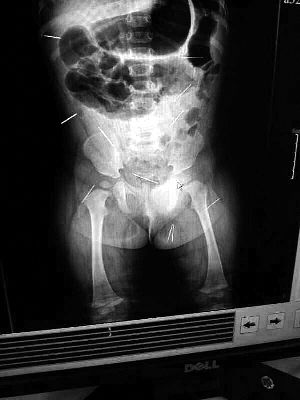

山東聊城11個(gè)月女嬰萱萱(化名)疑似被人以12根鋼針插滿臀部、腹腔等部位,昨天在兒童醫(yī)院會(huì)診后,醫(yī)生稱3根針靠近胸腔最危險(xiǎn),首批先行取出,預(yù)計(jì)將在下周二手術(shù)。孩子父母稱孩子一直由家人照顧,自家與他人并無冤怨。山東警方表示正在偵破中,不便透露案情。

“要不是當(dāng)初那幾個(gè)紅點(diǎn),可能到現(xiàn)在我們還不知道孩子身體里有鋼針!”昨天,在兒童醫(yī)院住院處,萱萱爸爸范先生稱,日前原本很愛笑的萱萱突然變得有些焦躁,一抱起來就哭,孩子母親偶然間在萱萱屁股上發(fā)現(xiàn)了幾個(gè)小紅點(diǎn)兒,原以為是蚊蟲叮咬,就醫(yī)結(jié)果卻讓人不寒而栗?!搬t(yī)院拍出的片子上,萱萱的體內(nèi)有12根鋼針,插滿臀部、腹腔、骨盆等各個(gè)部位?!狈断壬榻B,因?yàn)殇撫樢焉钊塍w內(nèi),要是孩子不哭鬧,他們很難發(fā)現(xiàn)。

北京晨報(bào)記者了解到,目前體內(nèi)的12根鋼針多分布在孩子的臀部,一根在腹部,其余3根在胸腔附近,其中一根很接近心臟?!耙?yàn)楹⒆犹。t(yī)生們害怕取針的時(shí)候?qū)λ斐蓚?,在胸腔附近?針可能會(huì)威脅她的生命”。